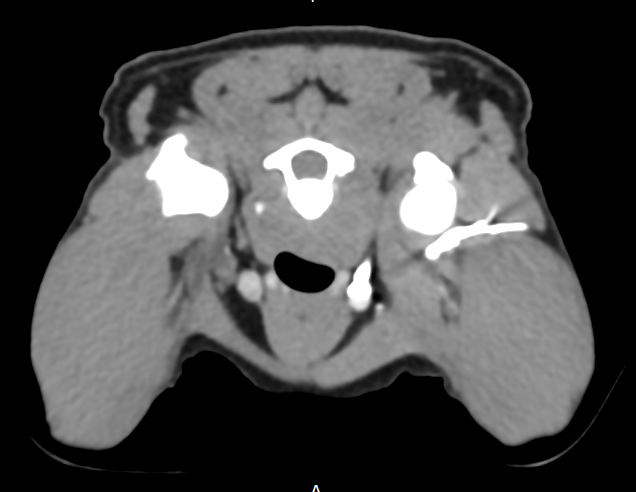

Denne godbiten har vi hatt på lager en liten stund, men vi har (heldigvis) hatt det travelt de siste ukene. Nå kommer endelig vårt nye kasus og vi vil gjerne benytte muligheten til å dele en fasinerende CT-studie som vi fikk inn fra Grong Dyreklinikk. Signalement: Blandingshund, hann, 8 år. Anamnese: Påkjørt for ca 5 år siden. Vondt høyre frambein og ble behandlet for fraktur i klobein. Hunden ble bedre, men så begynte han å halte på høyre frambein igjen. Klinisk mistenkes nerveskade.